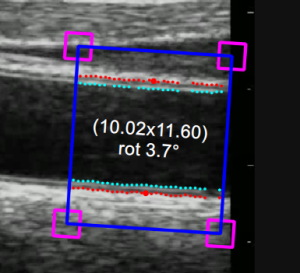

La région d'intérêt (ROI) en mode B correspond à la portion de l'image où sont calculés le diamètre et l'épaisseur intima-média (EIM). Les points d'interface lumière-intima et média-adventice sont affichés respectivement en cyan et en rouge au sein de la ROI. La ROI peut être déplacée, redimensionnée et/ou pivotée. Chaque modification de sa position, de sa taille et/ou de son inclinaison entraîne une réinitialisation de l'analyse.

• Cliquez à l'intérieur de la fenêtre vidéo et faites glisser jusqu'à ce que la ROI soit complète (la taille de la ROI est affichée dans le panneau Setup et graphiquement dans la ROI).